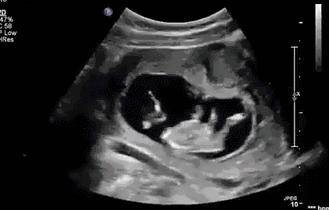

孕育生命是件神奇的事情,查出怀孕、第一次看到胎宝宝的样子、第一次感觉到胎动,都是孕妈感觉最幸福的瞬间。...